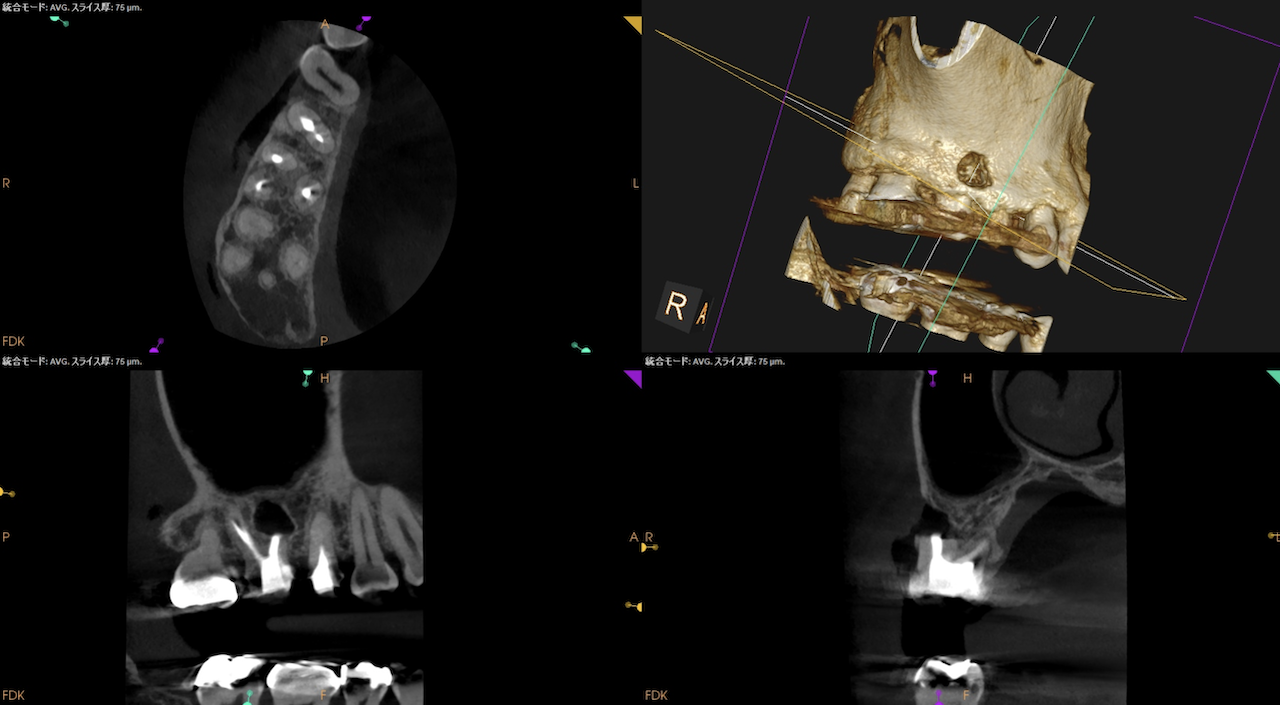

CBCT(2025.9.1)

#3

MB

DB

P

#4

B

#3のMBにはFileが折れ込んでいる。

#4はP根管が未着手だ。

#3に関してだが、MBの破折ファイルはちょうどカーブの変曲点を超えて根尖部に折れ込んでいる。

この時点で、それをいかにして除去するか?よりも、FileごとApicoectomyしたほうが時短になると私は考える。

CEJよりも10mm下方にMBのApexがあり、

破折したファイルごと除去しようと思えば3mmでなく4.5mmApexから切断したほうがいいだろう。